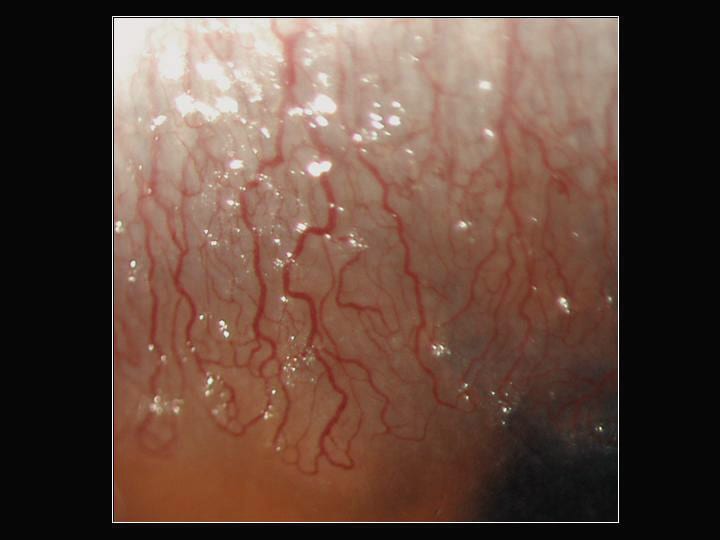

Figure 1. GS's left eye with mild bulbar injection. |

| Figure 2. Location and extent of the neovascularization. | |

| Figure 3. Elevated nodules just anterior to the neovascularization. |

Slit lamp examination of the symptomatic left eye showed mild superior bulbar inflammation as well as significant superior neovascularization with lipid leakage (Figures 1 and 2). The superior corneal epithelium was irregular with small, elevated gelatinous nodules adjacent to the areas of neovascularization (Figure 3). We also noted significant punctuate staining confined to the superior one-third of the cornea.